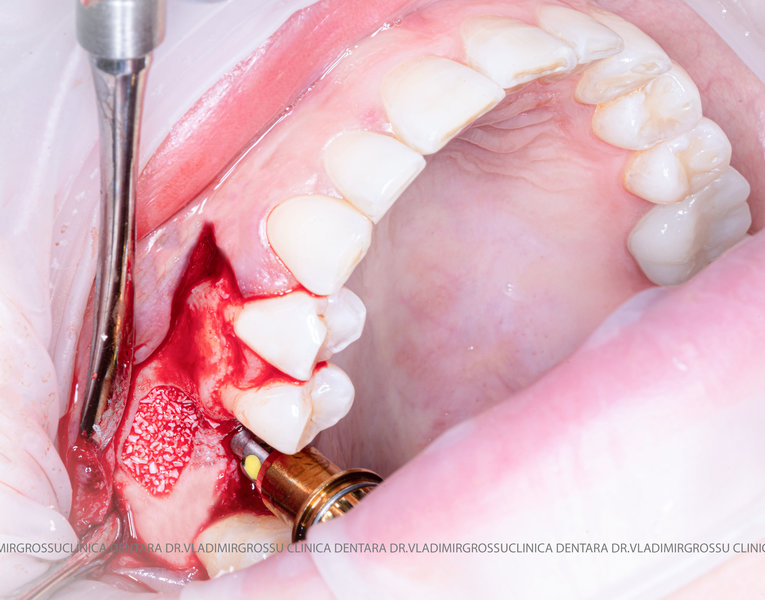

Stomatologia estetică reprezintă în prezent una dintre direcțiile principale de specializare a medicilor clinicii Dr. Grossu din Chișinău.Adiția sau augmentarea osoasă este o procedură chirurgicală prin care se refac defectele osoase rezultate în urma extracțiilor dentare, bolii parodontale sau traumelor dento-alveolare.

După extracția dentară, în intervalul de 6-12 luni, osul alveolar suferă un proces natural de remodelare, ceea ce conduce la scăderea volumului osos prin rezorbție. De aceea, inserția implantului dentar este ideală imediat după extracție sau, cel târziu, în primele 3-4 luni după aceasta.Scopul procedurilor de adiție osoasă este refacerea fundației osoase necesare pentru stabilizarea corectă a implantului dentar. Pentru ca un implant să reziste în timp la forțele masticatorii, este nevoie de o bază osoasă solidă și sănătoasă.

Procesul de refacere osoasă este complex, însă, simplificat, se bazează pe faptul că osul adăugat se integrează treptat, fiind înlocuit parțial cu os natural, oferind astfel suportul necesar implantului.

Adiția osoasă are un rol crucial pentru poziționarea corectă și stabilă a implanturilor dentare. Clinica stomatologică Dr. Grossu din Chișinău promovează o abordare chirurgicală estetică și predictibilă, adaptată fiecărui caz în parte.